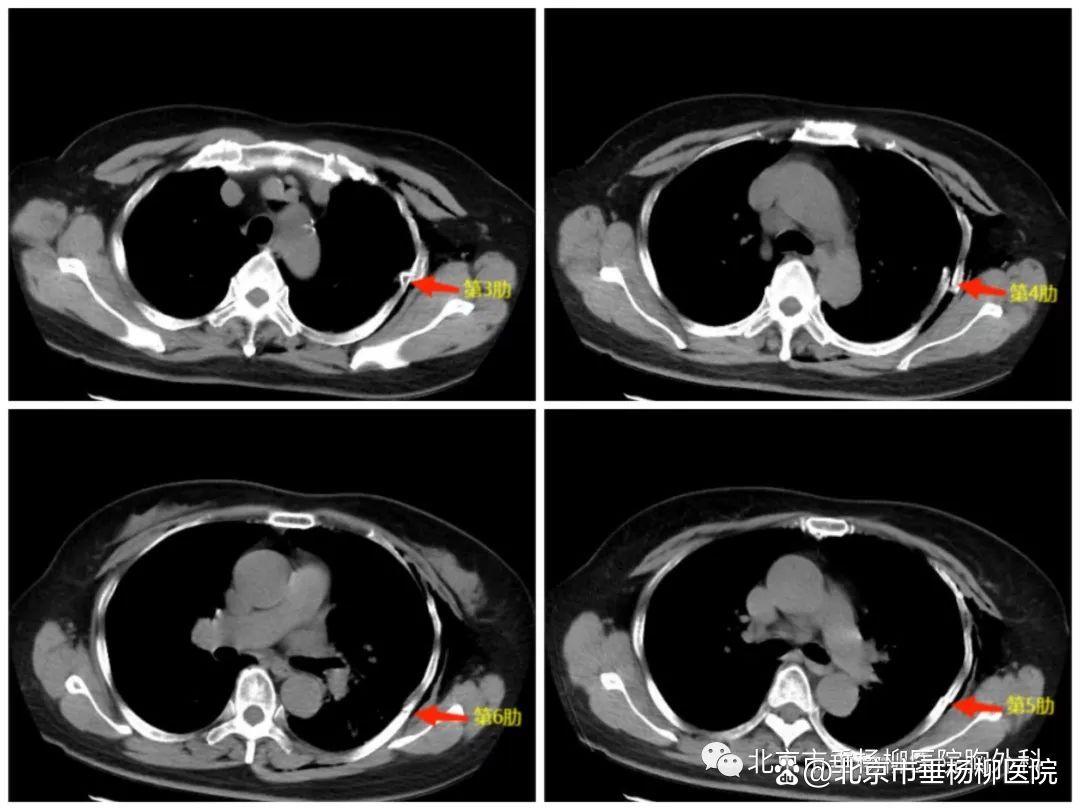

患者,女性,65岁,主因“摔伤致左侧胸部疼痛伴憋气半天”入院。患者半天前不慎摔倒,左侧后背部着地,伤口即感胸背部疼痛,伴有胸闷、憋气,就诊于我院,完善胸部CT检查,提示左侧3-6肋骨骨折,左侧气胸。急诊行左侧胸腔闭式引流术,患者骨折部位位于左侧肩胛骨后,科室商议后决定行胸腔镜微创骨折固定术。2023年8月4日全麻下行电视胸腔镜下肋骨骨折内固定术,术中固定第3-5肋,手术后恢复顺利,3天拔管出院。

胸部CT:红色箭头处为骨折部分